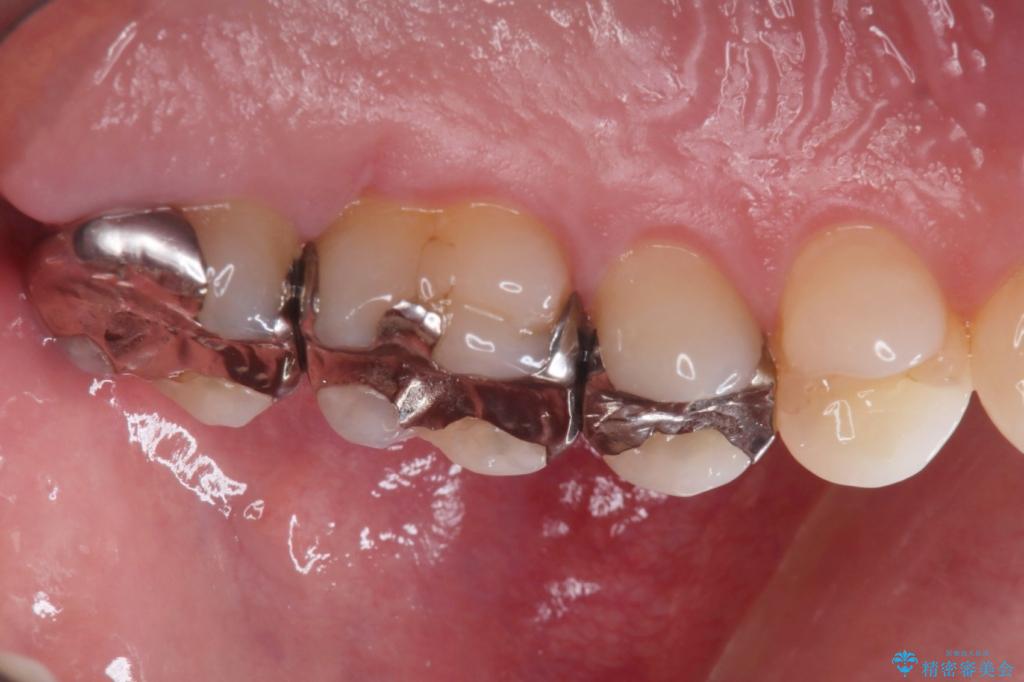

【メタルフリー】銀歯を綺麗な白い歯に

- 銀歯の入っている部分にフロスが引っかかるため、銀歯を適合の良い白いセラミックインレーにやりかえることを提案させていただきました。

一番奥の歯は銀歯に覆われている範囲が多いため、強度などを踏まえ被せ物にしました。

その他2本は詰め物です。